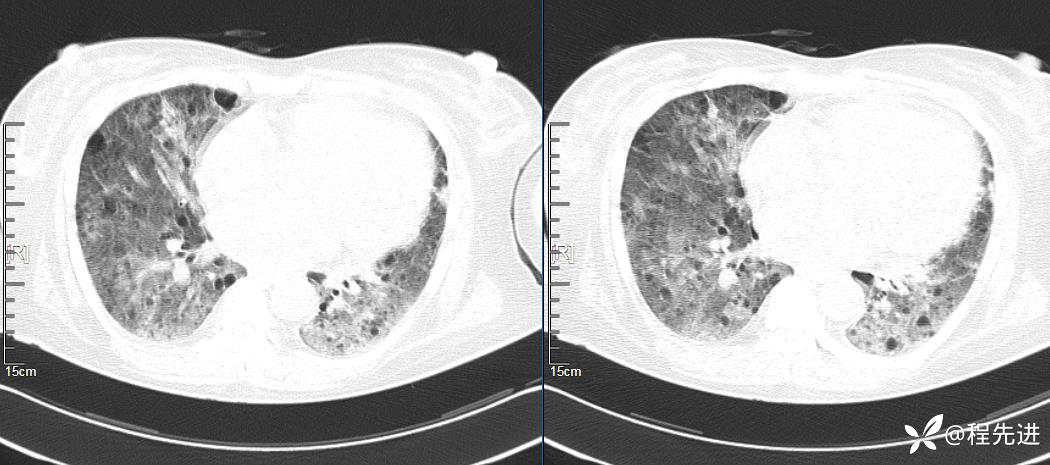

CT平扫(纵隔窗无特殊,就不上传了):

2、本例肺气囊分布有什么特点?肺气囊有无小叶核心?有没有间质纤维化及伴发结节?